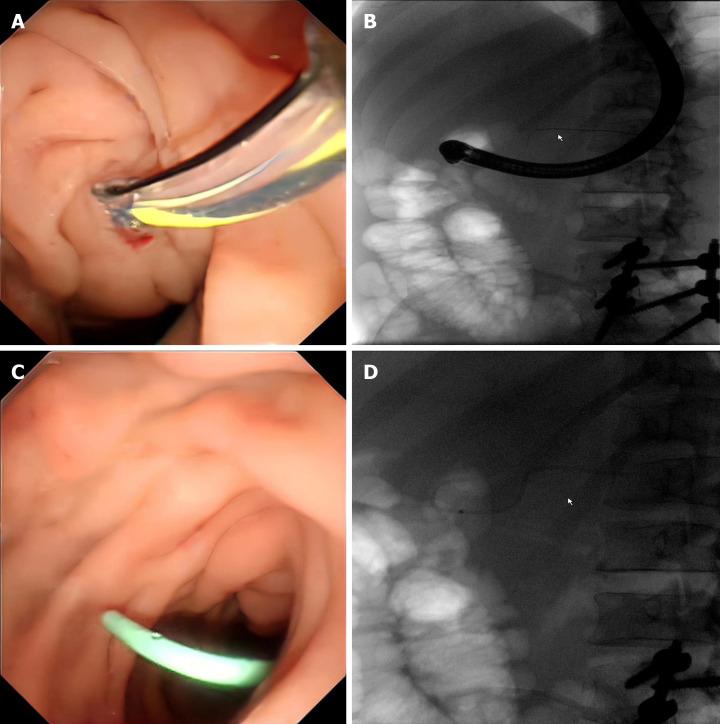

We report the case of a 43-year-old man who was admitted to the hospital with severe intake reduction due to early satiety 2 wk after treatment for acute pancreatitis; conservative treatment was ineffective, and a pancreatic pseudocyst was suspected on contrast-enhanced computed tomography (CT). Endoscopic ultrasonography (EUS) suggested hyperechoic necrotic tissue within the cyst cavity. The wall was not completely mature, and the culture of the puncture fluid was positive for A-haemolytic Streptococcus. Thus, the final diagnosis of ANC infection was made. The necrotic collection was not walled off and contained many solid components; therefore, the patient underwent EUS-guided aspiration and lavage. Two weeks after the collection was completely encapsulated, pancreatic duct stent drainage endoscopic retrograde cholangiopancreatography (ERCP) was performed, and the patient was subsequently successfully discharged. On repeat CT, the pancreatic cysts had almost disappeared during the 6-month follow-up period after surgery.

我们报告一例43岁男性患者,在急性胰腺炎治疗2周后因早饱导致严重进食减少入院;保守治疗无效,对比增强计算机断层扫描(CT)怀疑有胰腺假性囊肿。内镜超声检查(EUS)提示囊肿腔内有高回声坏死组织。囊壁未完全成熟,穿刺液培养A溶血性链球菌阳性。因此,最终诊断为ANC感染。坏死性积液未形成包裹且含有许多实性成分;因此,患者接受了EUS引导下的抽吸和灌洗。在积液完全包裹两周后,进行了胰管支架引流及内镜逆行胰胆管造影(ERCP),患者随后成功出院。术后6个月随访期间复查CT显示胰腺囊肿几乎消失。